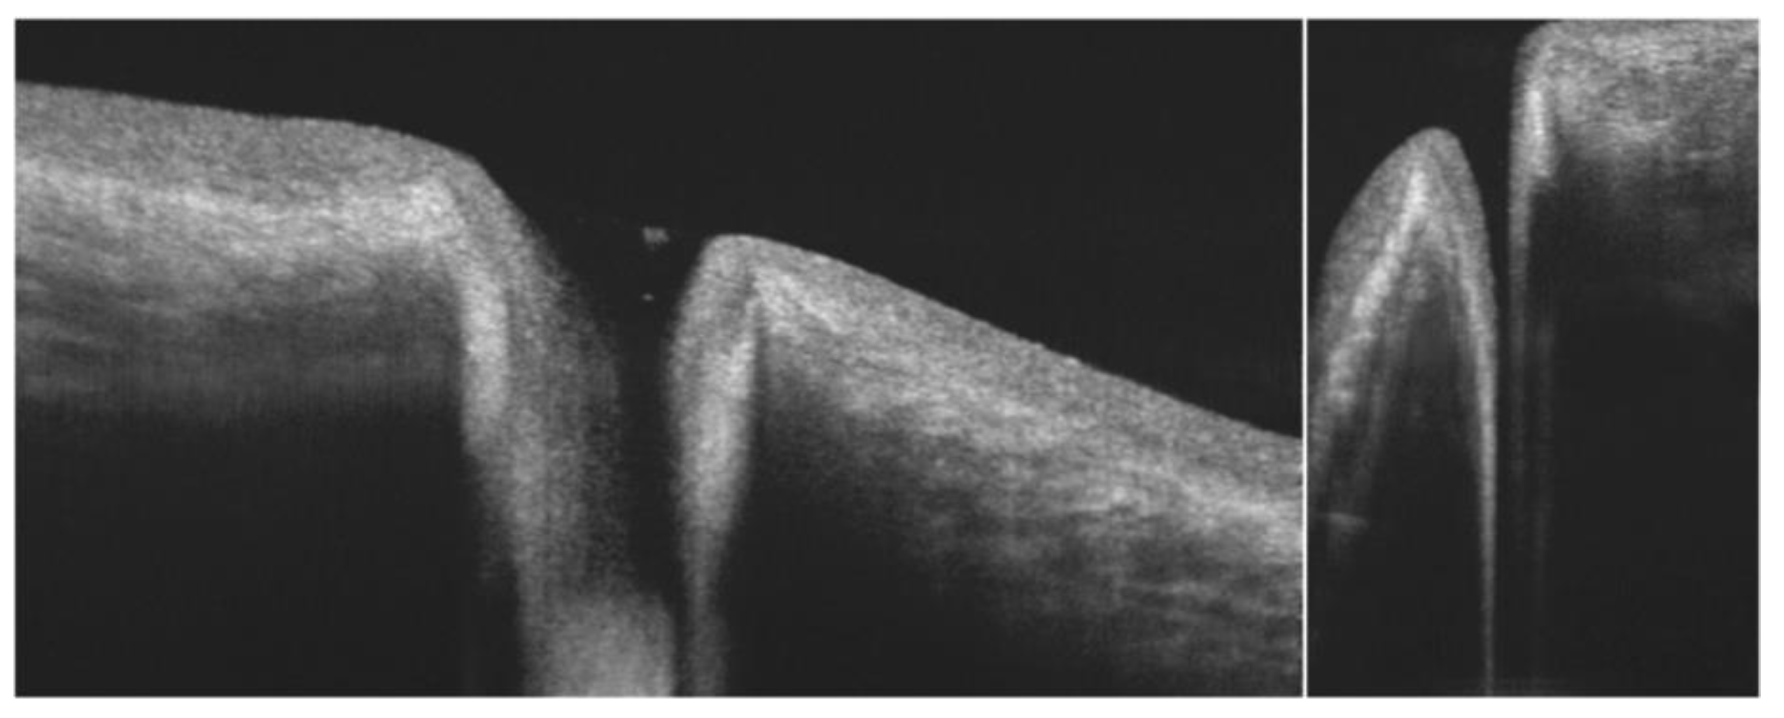

- Yokoi, N.; Bron, A.J.; Tiffany, J.M.; Maruyama, K.; Komuro, A.; Kinoshita, S. Relationship between tear volume and tear meniscus curvature. Arch. Ophthalmol. 2004, 122, 1265–1269. [Google Scholar] [CrossRef] [PubMed][Green Version]

- Wang, J.; Aquavella, J.; Palakuru, J.; Chung, S.; Feng, C. Relationships between central tear film thickness and tear menisci of the upper and lower eyelids. Invest. Ophthalmol. Vis. Sci. 2006, 47, 4349–4355. [Google Scholar] [CrossRef]

- Shen, M.; Li, J.; Wang, J.; Ma, H.; Cai, C.; Tao, A.; Yuan, Y.; Lu, F. Upper and lower tear menisci in the diagnosis of dry eye. Invest. Ophthalmol. Vis. Sci. 2009, 50, 2722–2726. [Google Scholar] [CrossRef]

- Chan, H.H.; Zhao, Y.; Tun, T.A.; Tong, L. Repeatability of tear meniscus evaluation using spectral-domain Cirrus(R) HD-OCT and time-domain Visante(R) OCT. Cont. Lens Anterior Eye 2015, 38, 368–372. [Google Scholar] [CrossRef]

- Ibrahim, O.M.; Dogru, M.; Takano, Y.; Satake, Y.; Wakamatsu, T.H.; Fukagawa, K.; Tsubota, K.; Fujishima, H. Application of visante optical coherence tomography tear meniscus height measurement in the diagnosis of dry eye disease. Ophthalmology 2010, 117, 1923–1929. [Google Scholar] [CrossRef]

- Tittler, E.H.; Bujak, M.C.; Nguyen, P.; Zhang, X.; Li, Y.; Yiu, S.C.; Huang, D. Between-grader repeatability of tear meniscus measurements using Fourier-domain OCT in patients with dry eye. Ophthalmic Surg. Lasers Imaging 2011, 42, 423–427. [Google Scholar] [CrossRef] [PubMed]

- Tung, C.I.; Perin, A.F.; Gumus, K.; Pflugfelder, S.C. Tear meniscus dimensions in tear dysfunction and their correlation with clinical parameters. Am. J. Ophthalmol. 2014, 157, 301–310.e301. [Google Scholar] [CrossRef]